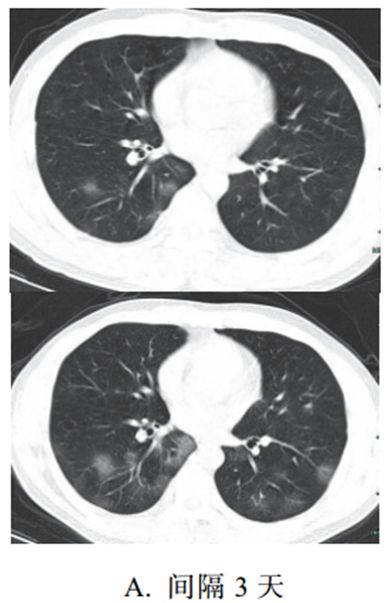

新冠肺炎大多数病例进展迅速,复查 CT 影像发生明显变化。

表现为病灶数目明显增多,范围明显扩大,密度增高,病灶分布由外周向中央推进。

根据既往 SARS 病理学机制,提示为肺泡腔内聚集大量细胞渗出液、间质内血管扩张渗出;肺泡连通起来形成融合态势(图 2-11)。

图 2-11 病灶数目增多、范围扩大 (A-D)